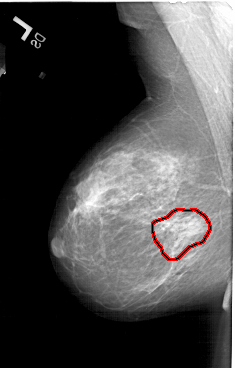

A_1217_1.RIGHT_MLO

LEFT_MLO LINES 5881 PIXELS_PER_LINE 3751 BITS_PER_PIXEL 12 RESOLUTION 43.5 OVERLAY

FILE: A_1217_1.LEFT_MLO.OVERLAY

TOTAL_ABNORMALITIES 1

ABNORMALITY 1

LESION_TYPE MASS SHAPE ARCHITECTURAL_DISTORTION MARGINS SPICULATED

ASSESSMENT 4

SUBTLETY 2

PATHOLOGY MALIGNANT

TOTAL_OUTLINES 1

BOUNDARY